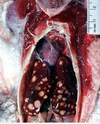

What are the molecular and morphologic changes of the image? ( MDx)

Clinical history and signs: 3 week old puppy, anorexia, dypsnea, abd pain upon palpation, normal rectal temperature

Multifocal, acute renal necrosis and hemorrhage or necrohemorrhagic nephritis

What is the etiology?

Clinical history and signs: 3 week old puppy, anorexia, dypsnea, abd pain upon palpation, normal rectal temperature

Canine herpesvirus-1 (CHV-1)

- red spots are from the virus targeting endothelium

What is the pathogenesis?

Clinical history and signs: 3 week old puppy, anorexia, dypsnea, abd pain upon palpation, normal rectal temperature

Transmission CHV-1 to pup at birth >incubation period of up to 1 week > virus replicates at temperature lower than 37C (98.6F) > endothelial cell tropism > multifocal necrosis in numerous organs